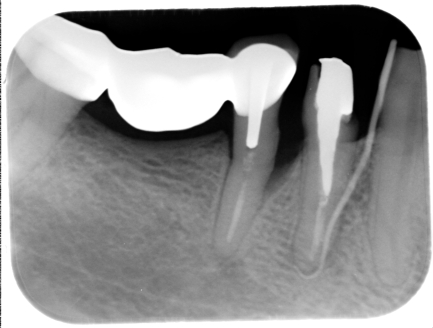

治療前

上圖術前可見明顯陰影與可見白色膿包,務必儘速治療